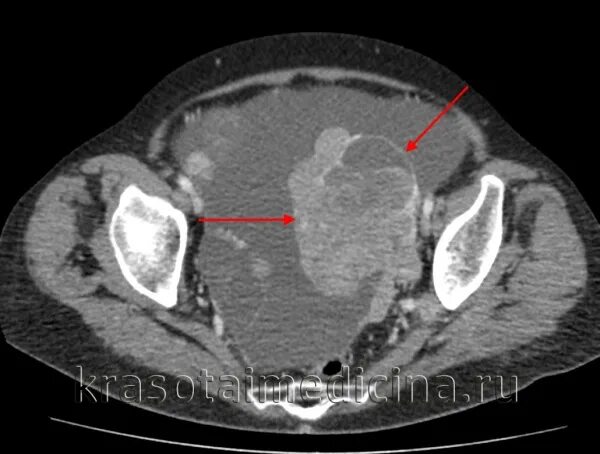

Метастазы в матке